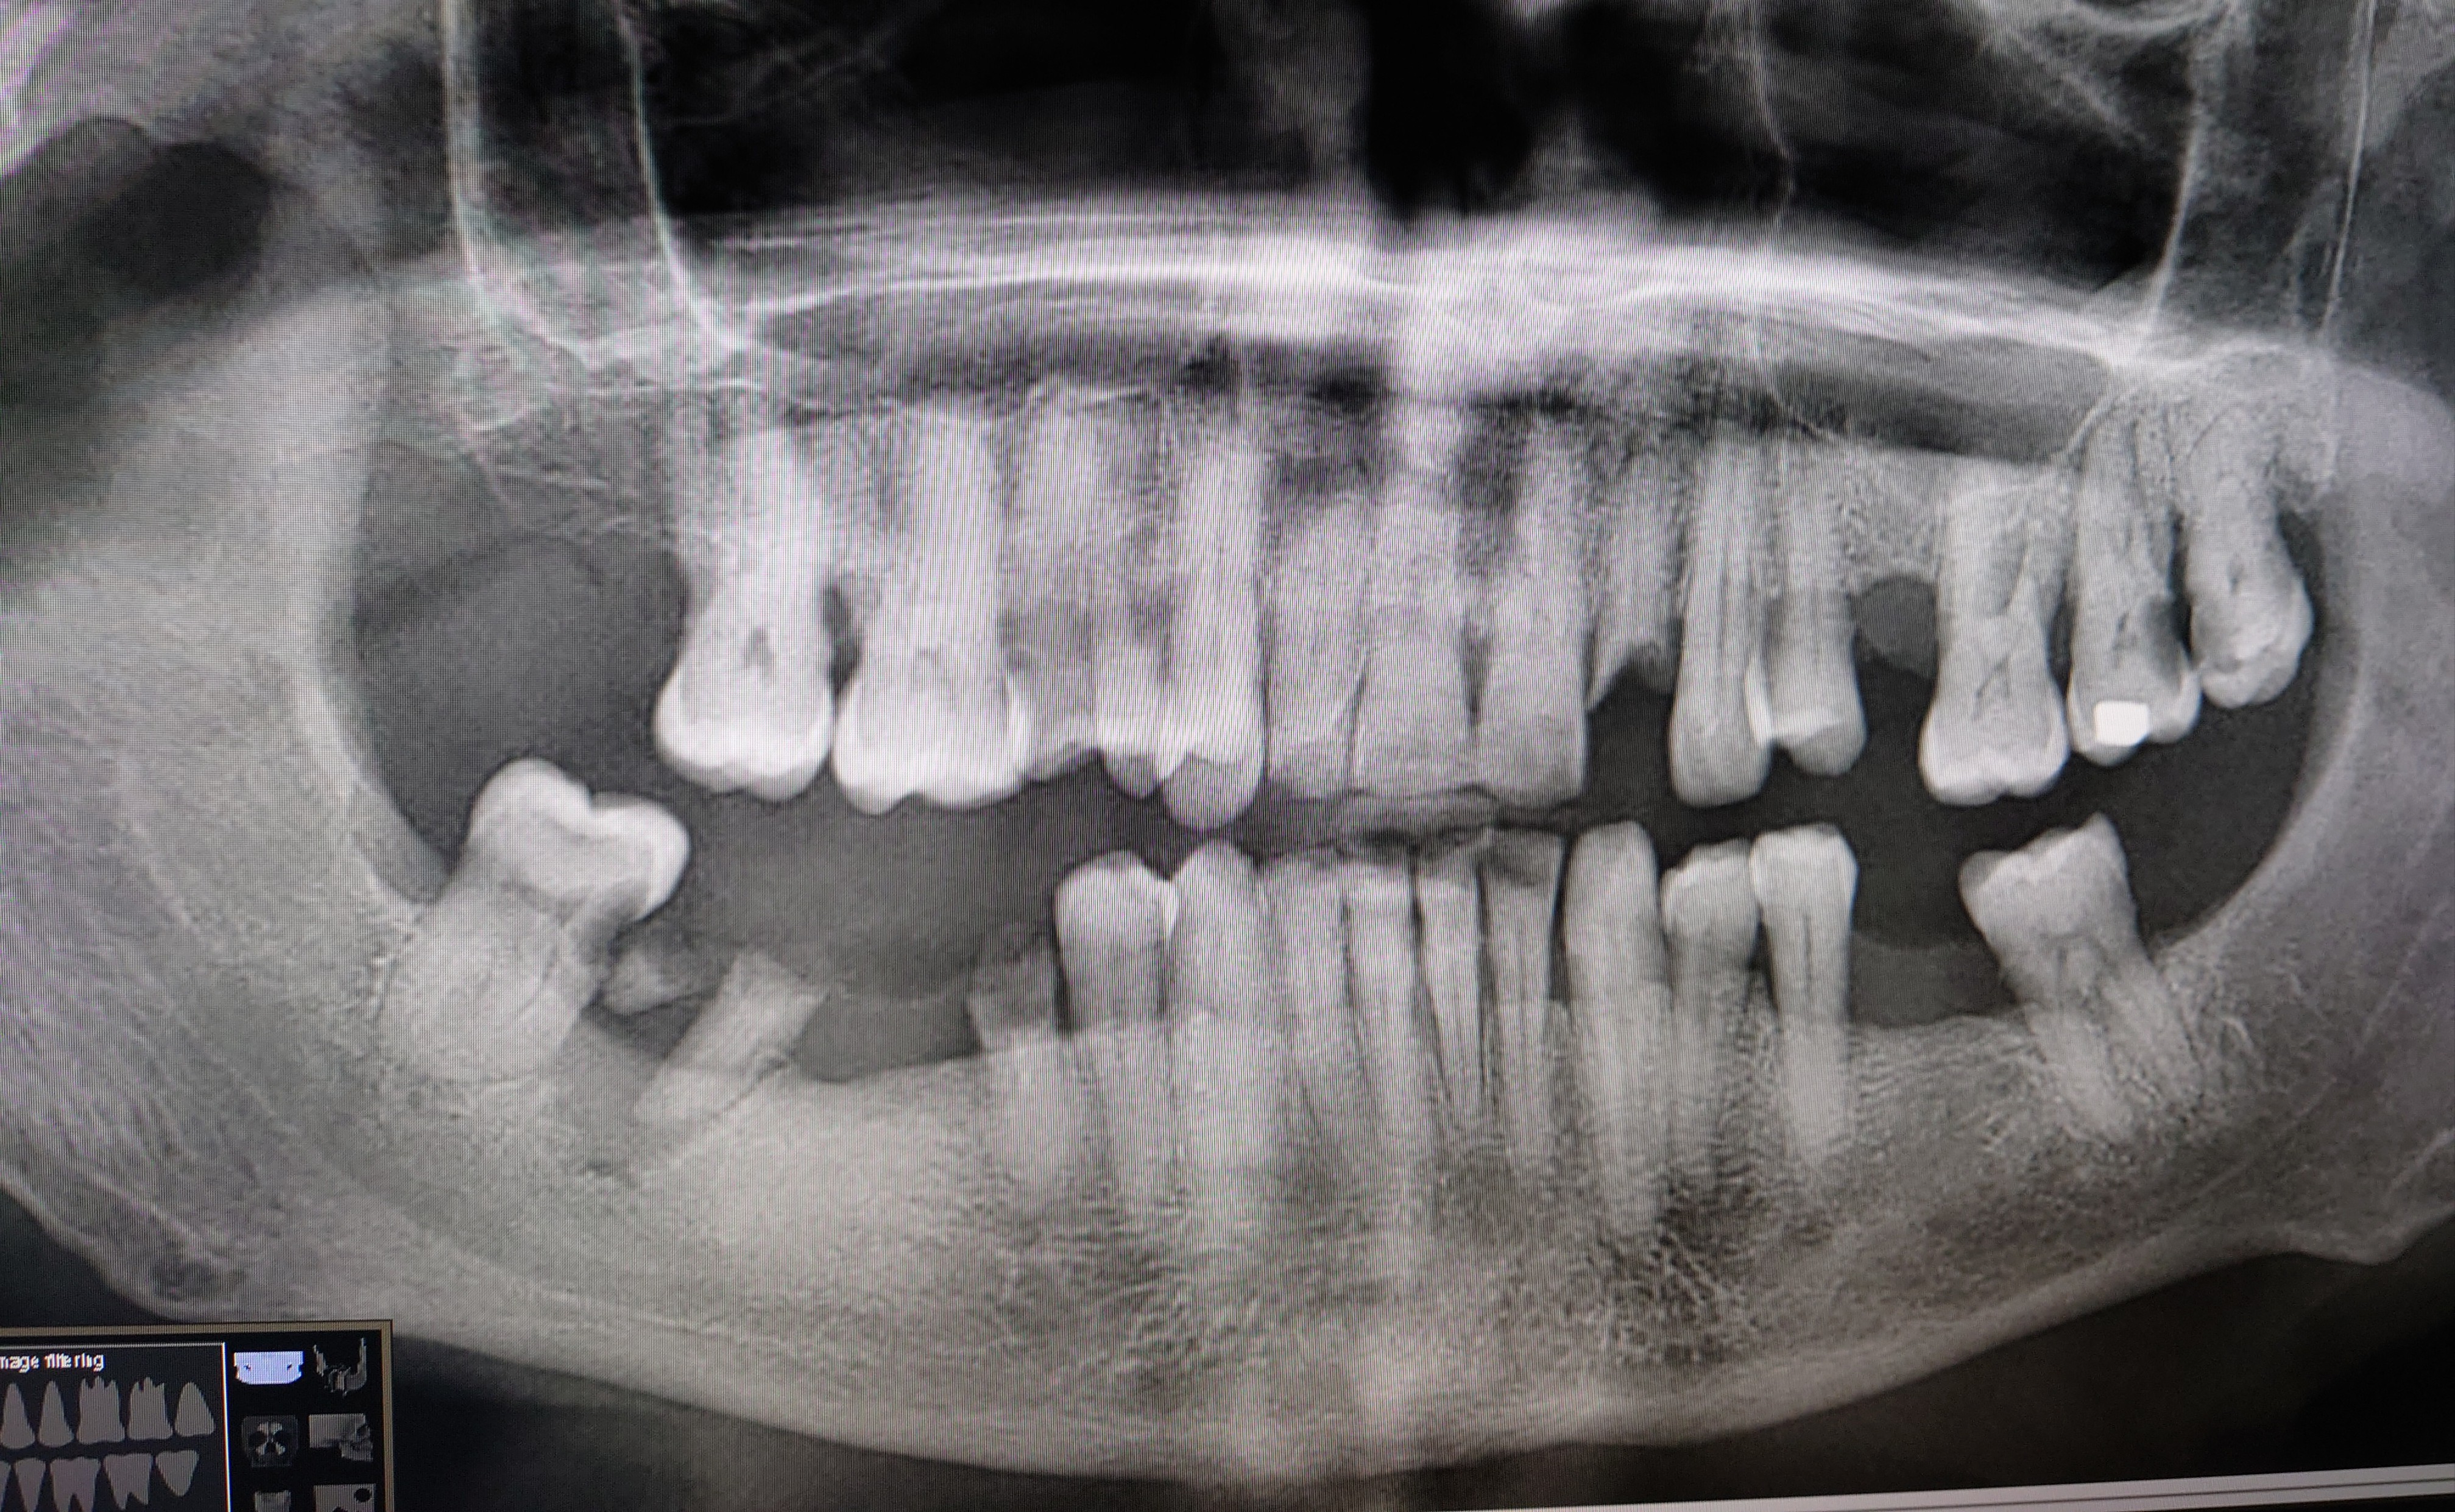

Also my teeth hurt so much, I took 1600mg ibuprofen and 500mg paracetamol in last 24 hours already. Woke up from super pain.

Take care of your teeth saaaaaar.

Your teeth hurting most likely means they're about to break. Go to the dentist, you might need to get a root canal and brush your damn teeth.